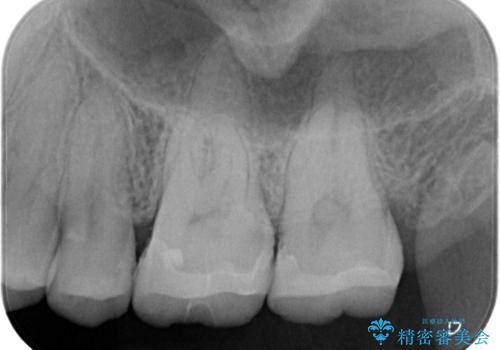

【メタルフリー】セラミックインレーの修復

- メタルフリーを希望された患者さんです。

金属を除去し虫歯の処置をしたあとセラミックインレーにて修復しました。

当院でのセラミックインレーは、ラバーダムを装着してセットしています。